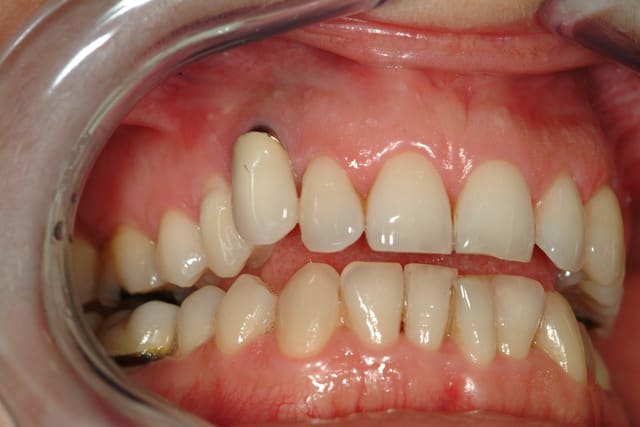

Patiente, 35 ans, d'un correspondant, reçue cet après midi.

Implant sur la 13 posé il y'à 15 ans.

La 13 était dans le palais, extraite qqs mois avant l'implantation.

problème esthétique depuis le départ...

Il me semble que c’est le liserai du pilier qui est visible, que l’ajustage la couronne soit perfectible et que l’on aperçoive légèrement l’implant.

L’espace entre 12 et 14 est trop faible pour aligner la 13 qui est trop courte sur bord incisif.

Voici les clichés de l'implant sur 13